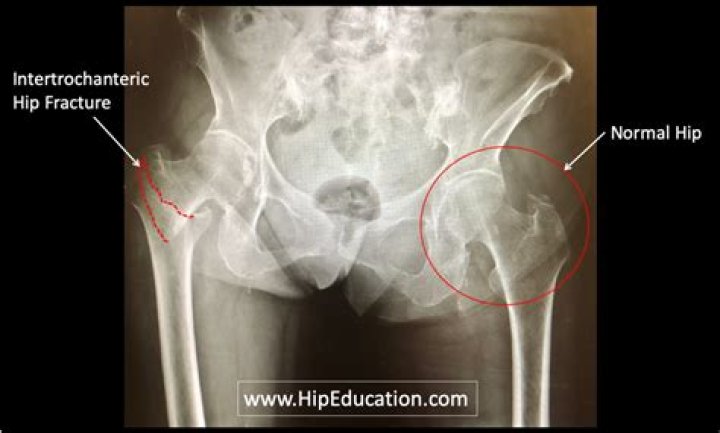

The top of your femur and part of your pelvic bone meet to form your hip. A broken hip is usually a fracture in the upper portion of your femur, or thigh bone. A joint is a point where two or more bones come together, and the hip is a ball-and-socket joint.

How do you know if you have a hip fracture?

Swelling or bruising on or near the hip.

• Being unable to bear weight on the hip.

• Having a hard time walking.

• Having pain in one leg,which appears shorter than the other leg or appears to point outward.